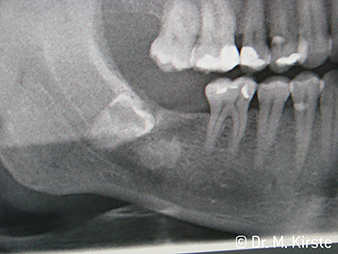

Kątnice WS-91 i WS-91 LG stanowią unikalne połączenie zalet kątnicy i prostnicy chirurgicznej (Zdj. 1). Powiększony kąt pomiędzy uchwytem a główką kątnicy do 45° znacznie ułatwia dostęp do pola operacyjnego zarówno do strony policzkowej jak i okluzyjnej (Zdj. 4). W efekcie radykalnie poprawia się komfort pracy np. podczas ekstrakcji zębów zatrzymanych, a poszerzone pole widzenia dodatkowo czyni zabieg bezpieczniejszym (Zdj. 6 i 7). „Wystarczy, że przekręcę nieznacznie główkę kątnicy i już mogę pracować niezwykle szybko i bezpiecznie w okolicy zębów trzonowych. Zalety nowych kątnic W&H mają szansę pogodzić zwolenników używania prostnic z lekarzami preferującymi kątnice ” Dr. Mario Kriste (Zdj. 2-5).

Resekcja wierzchołka to jeszcze jedno wskazanie do zastosowania kątnic WS-91 i WS-91 LG. Specjalnie zaprojektowany kształt zapewnia doskonałą widoczność podczas zabiegów w okolicy trzonowców w szczęce, a także poprawia jakość pracy u pacjentów z mikrostomią. Zastosowane w WS-91 LG oświetlenie miniLED+ dodatkowo doświetla pole zabiegowe światłem o jakości nieporównywalnie lepszej, od uzyskiwanego przy pomocy światłowodu.